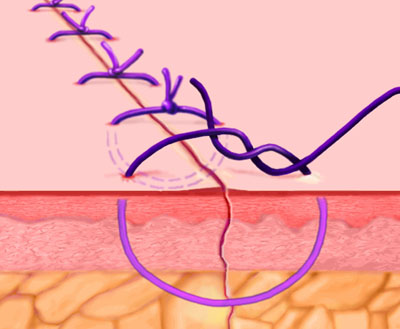

بخیه ای که در کشور ما با نام ساده یا simple شناخته شده است.

Interrupted Stitch

Each stitch is tied separately. May be used in skin or underlying tissue layers. More exact approximation of wound edges can be achieved with this technique than with the running stitch

Smead-Jones/Far-and-Near

A double loop technique alternating far and near stitches, and possessing greater mechanical strength than continuous or simple interrupted sutures. Commonly used for approximating fascial edges, especially for patients at risk for fascial disruption or infection

Continuous Locking, or Blanket Stitch

A self-locking running stitch used primarily for approximating skin edges